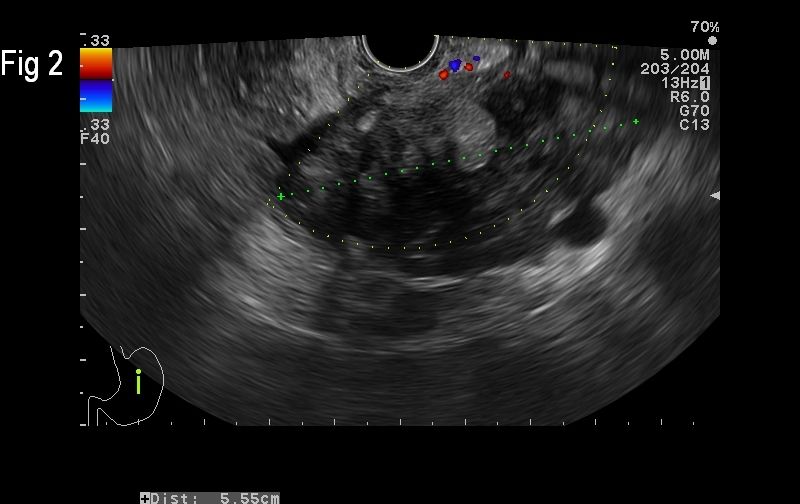

Figure 2. EUS demonstrates the primary tumour in the pancreas as a heterogenous hypo-and hyperechoic mass

Pancreatic neuroendocrine tumours (pNET) are considered rare lesions with an incidence of less than 1 per 100 000 person-years. Five-year survival is about 55% when the tumours are localized and resected, but only about 15% when the tumours are not resectable (1). In advanced stages of this disease, as many as 50% of the patients with pNET have already developed metastases in the moment of initial diagnosis, whilst the presence of liver metastases is the major determinant of survival (2). We present a case of a neuroendocrine tumour of the pancreas with liver metastases, imaged with grey-scale, colour Doppler, contrast-enhanced ultrasound (CEUS) and endoscopic ultrasound.